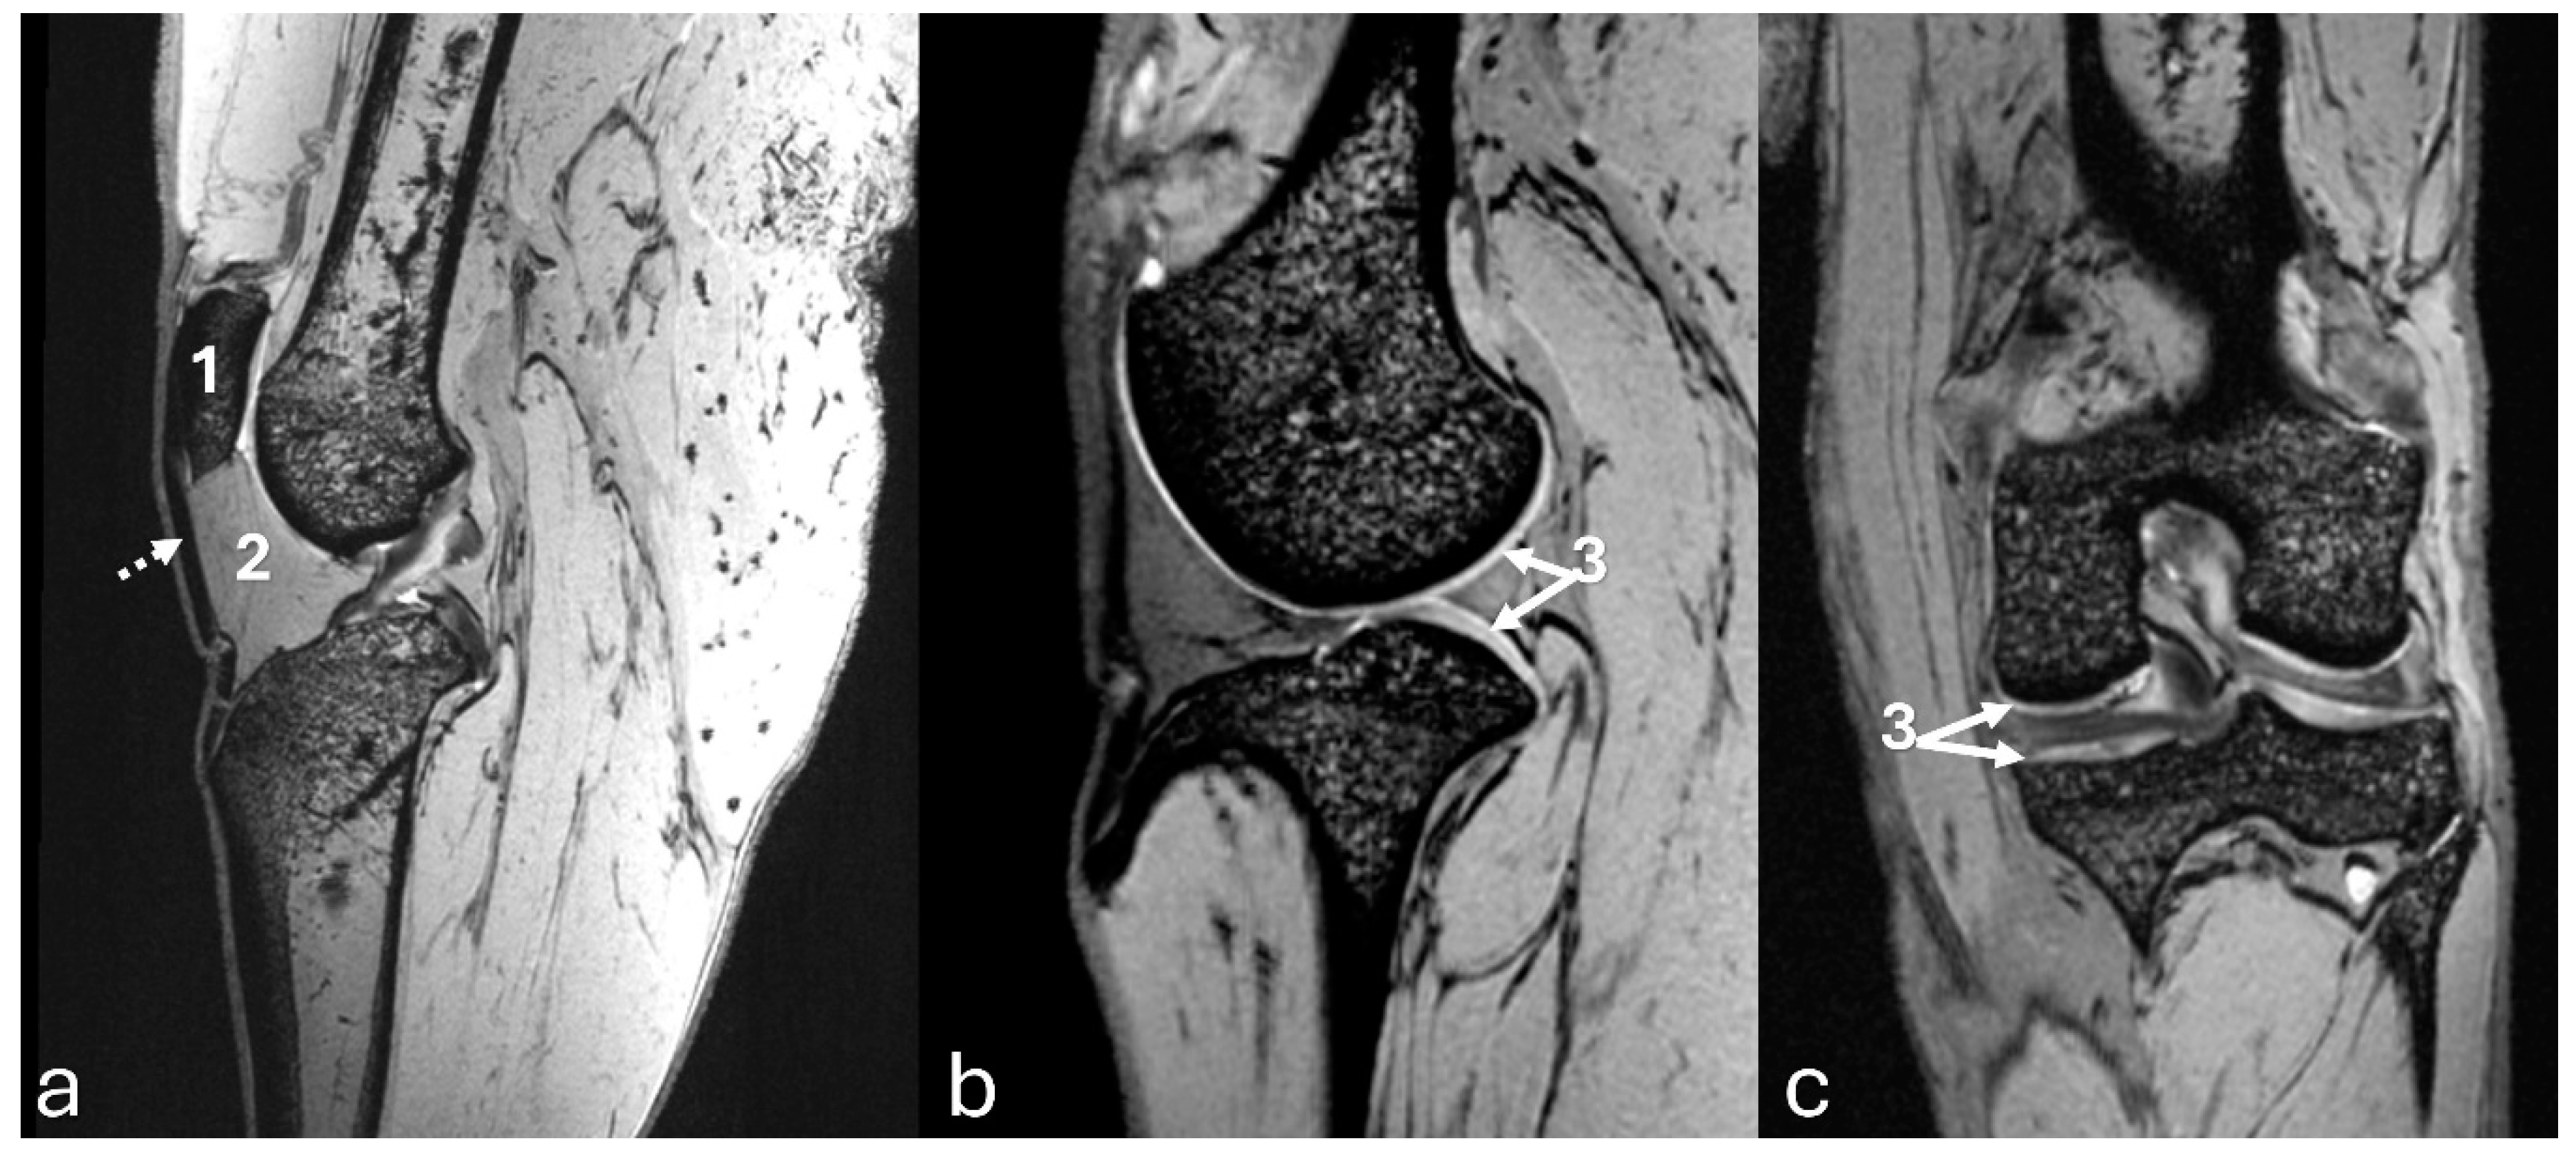

Figure 4. Computed tomography images of an adult puma stifle joint (Puma concolor). Sagittal (a) and dorsal planes (b), and a cranial view of the 3D reconstruction (c). Observe mineralization of the medial meniscus (arrow).

The 3D reconstruction of CT images (Figure 2c) revealed, in a cranial view, the patella as a raindrop-shaped structure with a wider base than the apex, positioned in the symmetrical trochlear groove. Meniscal mineralization was identified in the stifles of the same four animals as a hyperdense portion in the medial compartment. The caudal and lateral views displayed the lateral and medial fabellae in the epicondylar region of the lateral and medial condyles, respectively, with the lateral one being larger (Figure 2d). Other bone structures showed similar patterns as seen in radiographic images. Multiplanar and cross-sectional images allowed identification of the patella, infrapatellar fat, cranial cruciate ligament (from the caudal portion of the femur to the cranial area of the tibia), caudal cruciate ligament (from the cranial aspect of the femur to the popliteal margin of the tibia) and meniscofemoral ligament (Figure 3). The menisci were more difficult to identify, but those with partial mineralization were easily visualized (Figure 4). The fabellae and sesamoid of the popliteal were also identified; all had a thin cortical layer.

Figure 3. Sagittal computed tomography images on sagittal plane of an adult puma stifle joint (Puma concolor). (a) Cranial cruciate ligament. (b) Caudal cruciate ligament. (c) Meniscofemoral ligament.